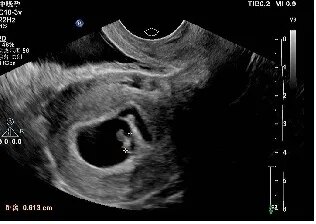

2019年10月18日一超:宫腔内见胚囊,大小17*21*22mm,胚芽长6mm,胎心136次/分。血β-HCG 56778.4、孕酮27.35、雌二醇 373.12。

2019年10月29日二超:宫腔内见胚囊,大小31*21*31mm,胚芽长18mm,胎心167次/分。二超当天顺利毕业,转往产科建卡!

一超二超照片